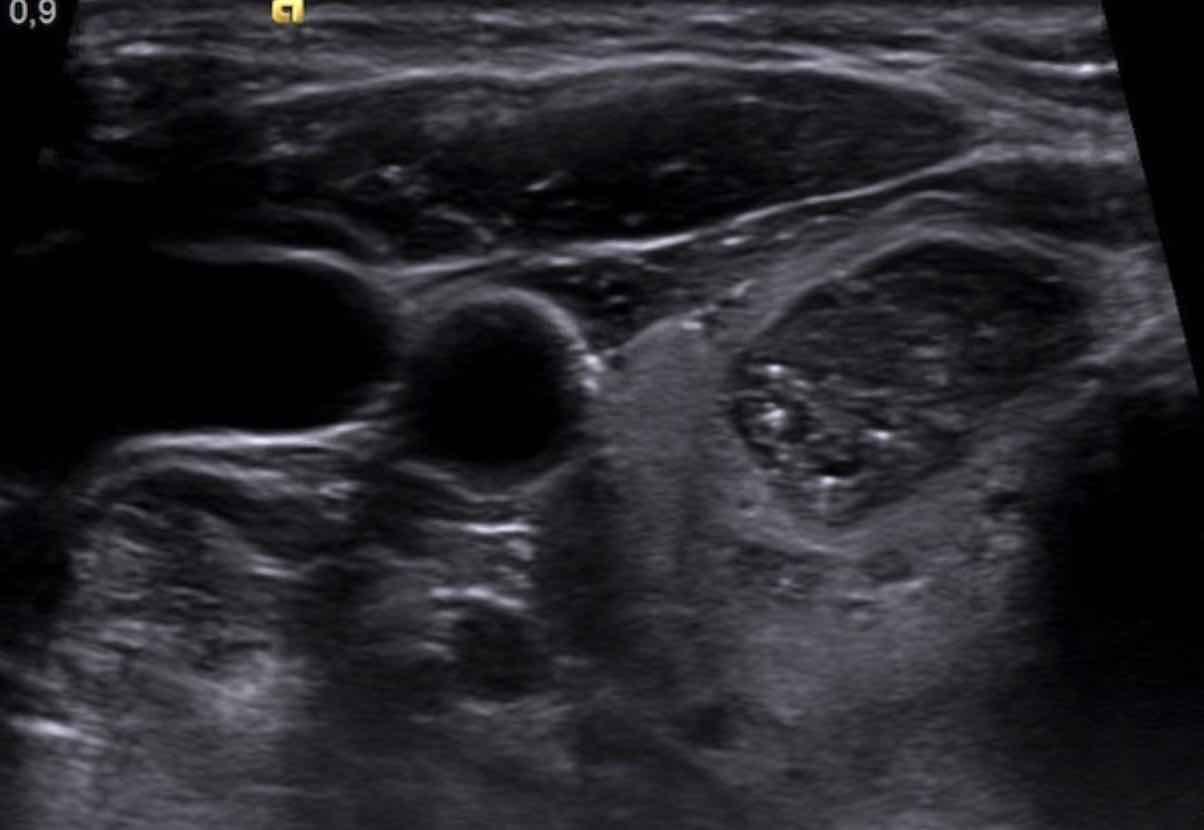

Microcalcifications

Các ổ tăng âm dạng chấm, còn được gọi là vi vôi hóa, là yếu tố dự báo mạnh cho ác tính và được tính 3 điểm trong hệ thống TI-RADS.

Từ điển thuật ngữ của Hiệp hội Điện quang Hoa Kỳ (ACR) phân loại chi tiết hơn về nhóm này, vì các tiêu điểm tăng âm cũng có thể xuất hiện trong mô tuyến giáp bình thường.

Các tiêu điểm tăng âm dạng chấm chỉ nên được phân loại như vậy khi chúng có thể xác định rõ ràng và nằm hoàn toàn trong phạm vi nhân.

Ngoài ra, các hiện tượng đuôi sao chổi nhỏ có chiều dài dưới 1 mm cũng được xếp vào nhóm vi vôi hóa.

Điểm TI-RADS: 3 điểm.